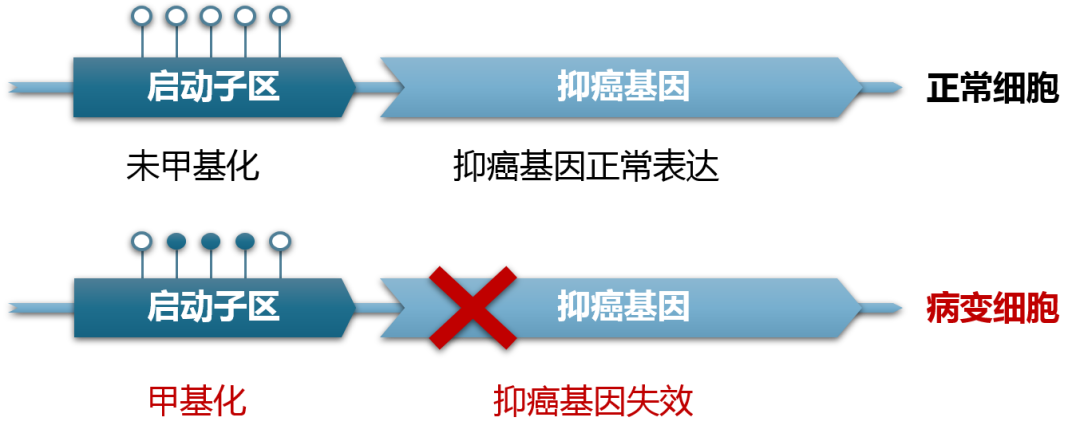

DNA的異常甲基化與癌癥的發生和發展有著很大的相關性。凋亡的癌癥或息肉細胞中的DNA進入血液、糞便、唾液等特定樣本中,通過檢測特定樣本中甲基化DNA水平可發現癌癥。